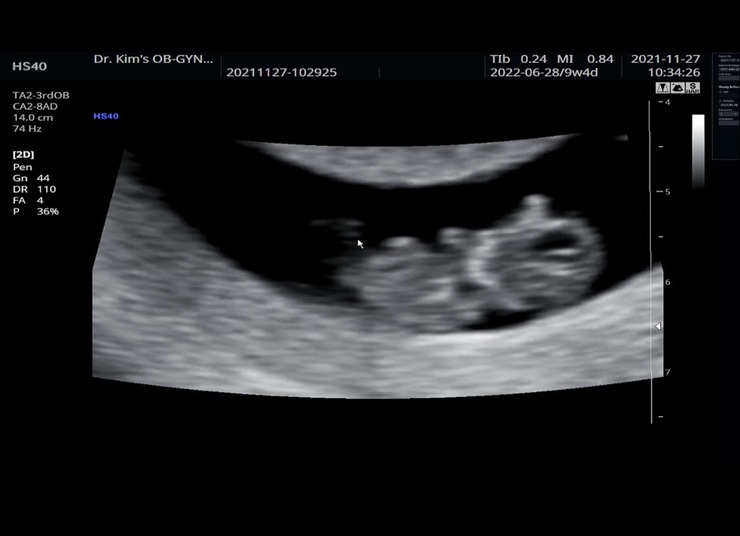

찰떡이 9주4일 젤리곰 보다

9주3일 난임병원 졸업 8주까지 마리아 다니다 드뎌 졸업했다. 난 그 유명하신 김건우 산부인과로 전원하고 ...